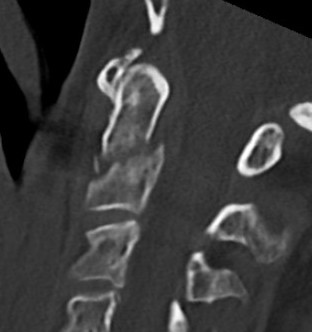

Type III

Definition

Through the body of C2

May involve portions of C1 or C2 facets

High healing potential

Non operative management

- 212 patients with Type III dens fracture

- average age 72, 20% lived independently

- 95% treated nonoperatively

- 5% required surgery

- 25 patients with Type III dens fracture

- hard collar or halo vest

- 22/25 (88%) united

- nonunion associated with increased coronal tilt and lateral mass gap > 2mm